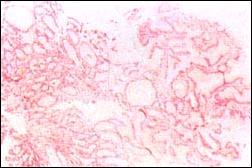

El pólipo tipo III de Nakamura, que en los primeros tiempos en el Japón se denominó por su autor como epitelio atípico, actualmente cobra carta de ciudadanía llamándosele simplemente pólipo tipo III o flat adenoma (este adenoma Fig 6 y foto 14, 15 y 16: la foto 2 es el original presentada por Nakamura.

Foto 14

Foto 15

Foto 16

Las microfotografías 15 y 16, de nuestra casuística, muestran pólipos catalogados como Nakamura III. Presentan una apariencia sesil. histologicamente peculiar con estructura en 2 capas; la capa superior consiste en glándulas displásicas, simulando glándulas de Lieberkuhn, mientras la capa inferior presenta glándulas pilóricas no displásicas y numerosos quistes.